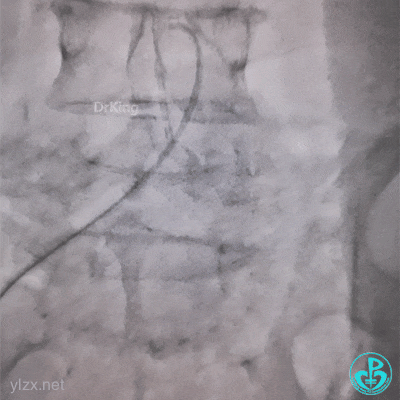

J-W软头端无法通过管子。

换硬头端(铤而走险、不常规推荐)。

管子头还是打不开,调整一下。

打折处通了,换软头端(直头端不敢出GC)。

管子头段直啦。

拉出来了。